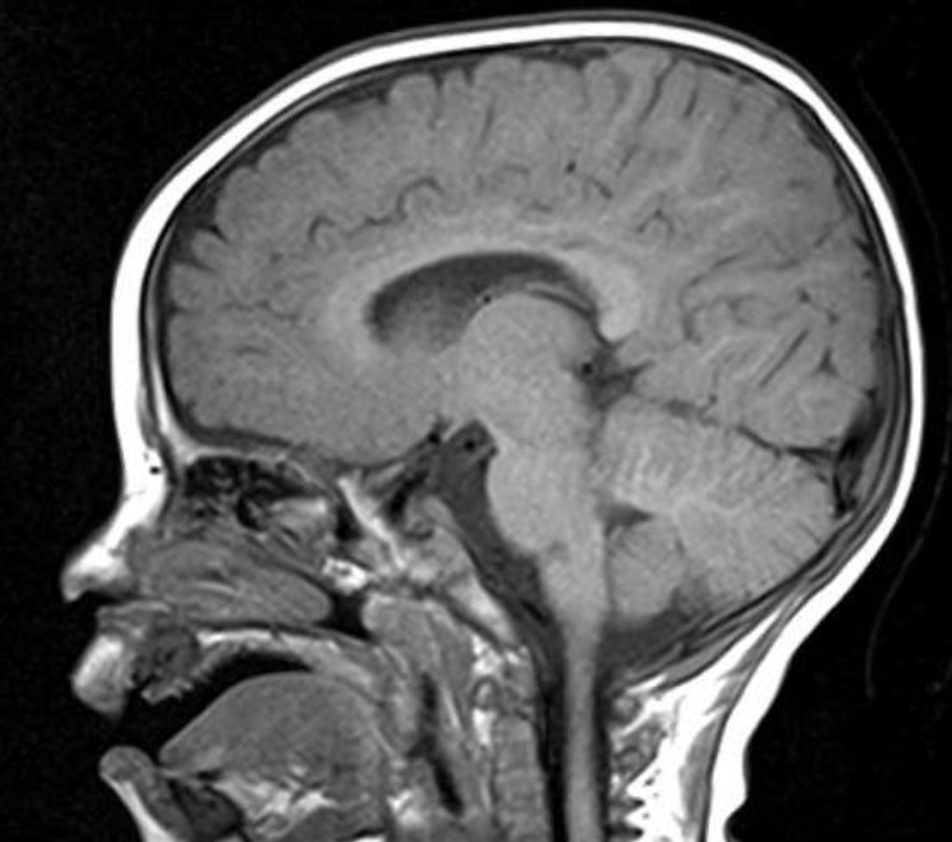

- Exame neurológico, cefaliátrico e FO inocentes. Trazia RM encéfalo normal

- RM Encéfalo